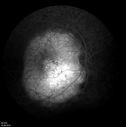

Patient is a 9 y.o. female who presented with blurred vision OD. On initial presentation VA = 20/200 OD (PH 20/60). Over the past 3 years patient has received intravitreal Avastin x 2 for Choroidal Neovascularization. Current VA =20/25 OD.

Choroidal Osteoma814 viewsYoung girl with vision loss from osteoma.00000